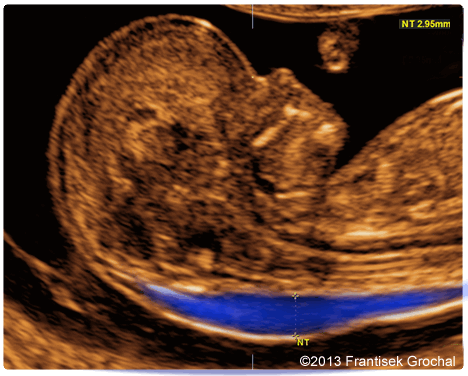

Перед измерением ТВП врач измеряет длину плода, то есть его КТР. Это крайне необходимо, потому что толщина воротникового пространства меняется в зависимости от срока беременности. Потом эхографист выводит на экран верхнюю часть туловища и головку плода строго в боковой проекции, при этом в одном срезе должны быть одновременно кости и кожа спинки носа, полости 4 желудочка и кость верхней челюсти. Используя масштабирование увеличивает область шеи. Затем измеряет наибольшую толщину скопления жидкости по задней поверхности шеи под кожей. Жидкость изображается на экране черным цветом, а кожа и мягкие ткани белыми. После проведенных измерений врач сравнивает полученный результат с нормативной таблицей.

Синим цветом на фотографии УЗИ выделено воротниковое пространство, толщина которого является важным параметром.